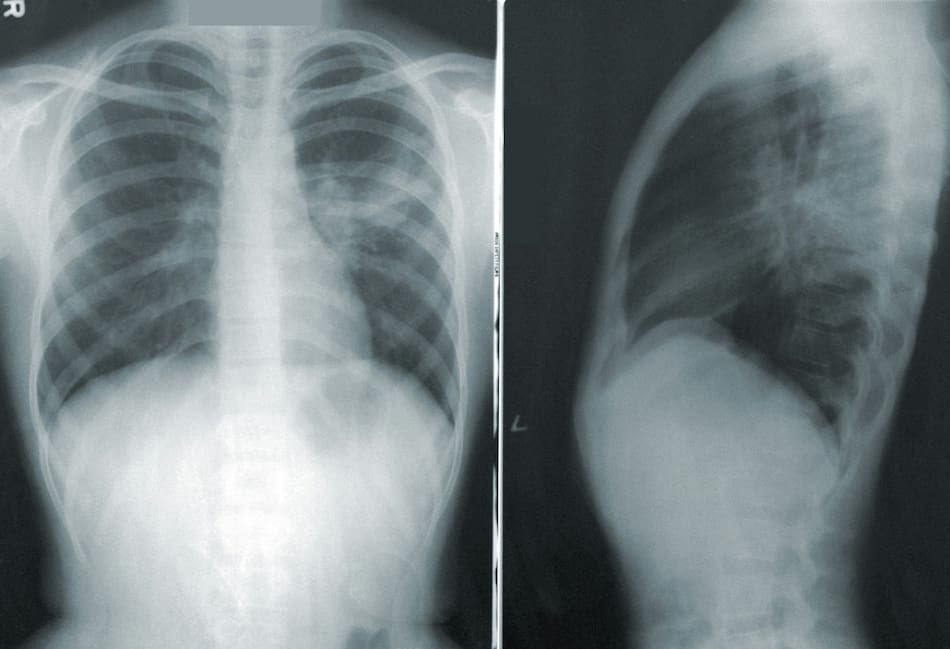

Radiografía de pulmones. Foto: Unsplash.